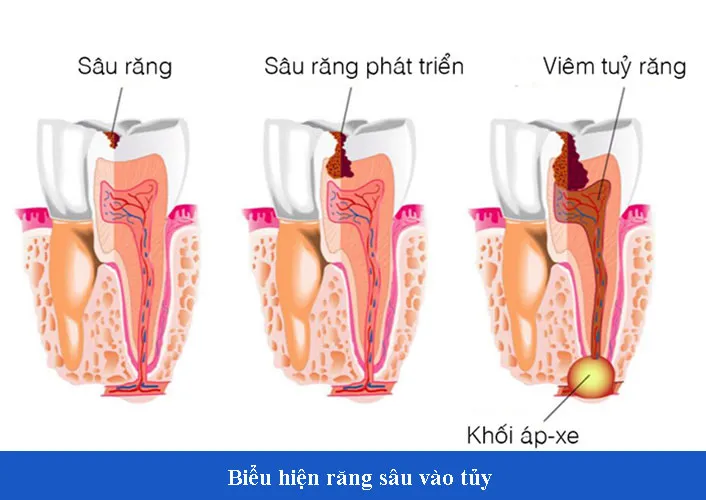

Răng sâu vào tủy là một bệnh lý răng miệng cực kỳ nguy hiểm và gay ra rất nhiều ảnh hưởng nghiêm trọng đến sức khỏe răng miệng của con người. Đây là hiện tượng những vi khuẩn gây sâu răng đã tấn công và phá hủy lớp men răng, ngà răng rồi xâm nhập tận vào bên trong tủy của răng. Chính vì vậy mà phần tủy của răng sẽ bị chế, bị viêm, thậm chí là gây ra hiện tượng viêm tủy xương, phá hủy toàn bộ cấu trúc của răng vĩnh viễn. Thậm chí nếu răng vào vào tủy không được điều trị kịp thời và dứt điểm thì còn có thể lây lan cả sang những răng khác nữa.

Ở giai đoạn đầu khi vi khuẩn sâu răng mới tấn công và xâm nhập vào phần tủy răng gây ra nhiễm trùng tủy răng và xung huyết tủy. Chính vì thế mà bệnh nhân có thể dễ dàng cảm nhận được những cơn đau răng và ê buốt đến nhức óc, những cơn đau thường kéo dài liên tục.

Tuy nhiên nếu người bệnh vẫn không chú ý nhiều đến dấu hiệu này, vẫn chủ quan và tự mình điều trị bằng những phương pháp như uống thuốc thì sẽ khiến cho phần tủy răng bị chết. Khi mà tủy răng đã chết thì các mạch máu và dây thần kinh cũng sẽ không còn cảm nhận được cảm giác nữa. Chính vì vậy mà người bệnh cũng sẽ không còn cảm nhận được những cơn đau răng và ê buốt nữa.

Khi không cảm thấy đau nữa người bệnh sẽ nghĩ là mình đã khỏi được bệnh. Tuy nhiên lúc này tủy răng đã chết, răng sẽ không còn bất cứ cảm giác nào nữa, nhưng vi khuẩn sâu răng vẫn sẽ cứ tiếp tục tấn công và phá hủy phần chân răng còn lại. Gây ra những hậu quả như áp xe ổ chân răng, viêm ổ xương răng và thậm chí là gây lây lan sang cả những răng bên cạnh.